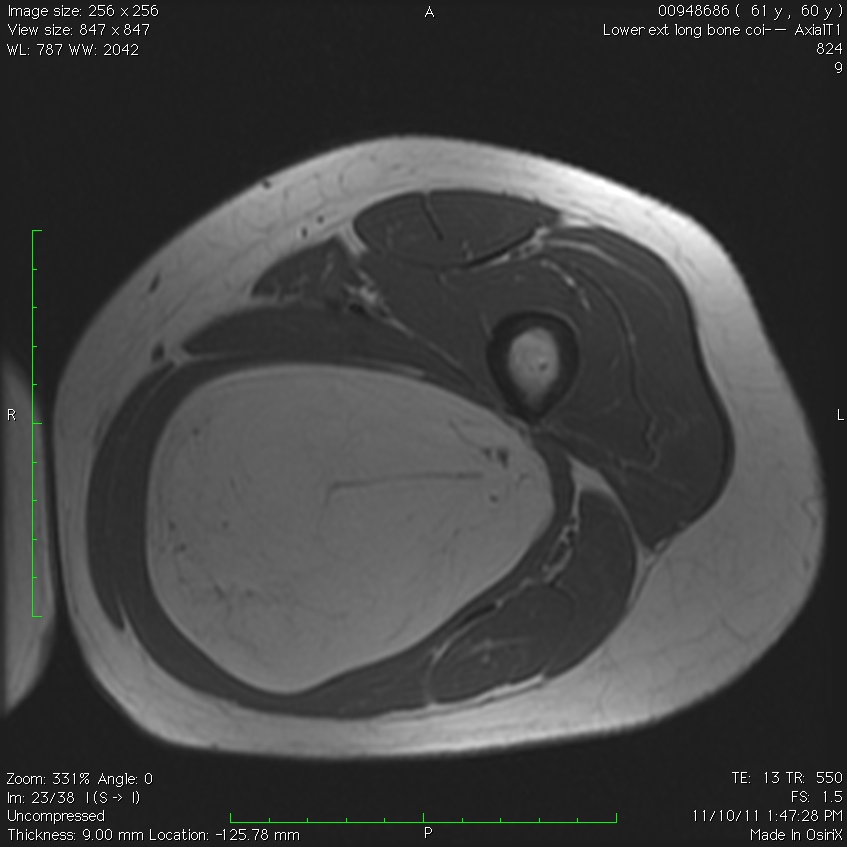

MRI

• Follows the signal characteristics of subcutaneous fat on all sequences

• T1: High Signal

• T2: Intermediate Signal; Low Signal with Fat Suppression

• Minimal or No enhancement with gadolinium

Fig. 1A, 1B, 1C, 2A, 2B, 2C: MRI of a lipoma: T1- weighted images shows an homogeneous mass in the posterior compartment of the thigh with high signal, saturates on fat saturated sequences with no or minimal enhancement. On T2-weighted images demonstrate an intermediate signal on FSE T2, saturates (becomes dark) on fat saturated sequences.